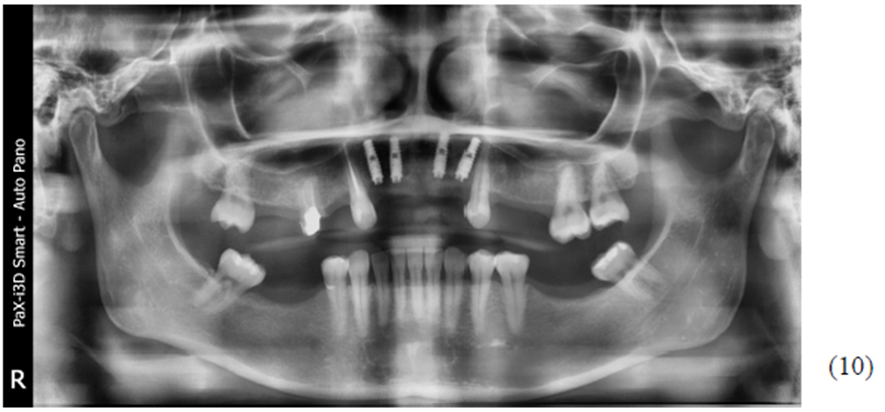

Após quatro meses, uma nova radiografia panorâmica foi realizada para planejamento reabilitador protético, onde nenhum sinal de anormalidade foi observado. (Figura 10).